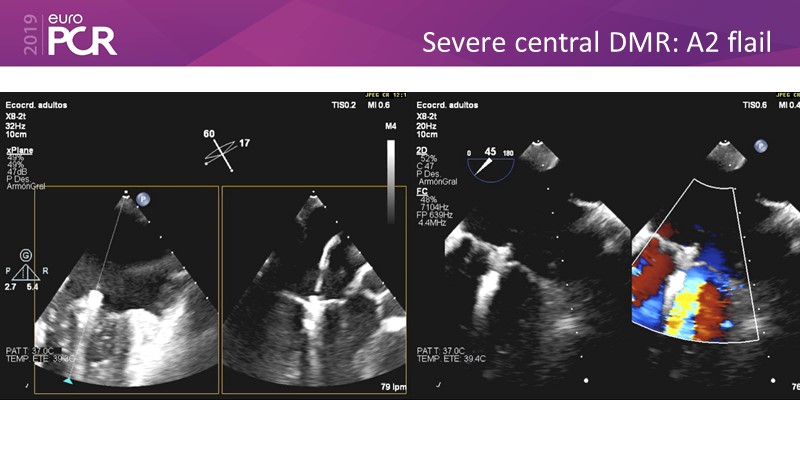

- To learn how will product innovation (Mitraclip NTR / XTR) drive improvement in procedural and clinical outcomes (EXPAND)